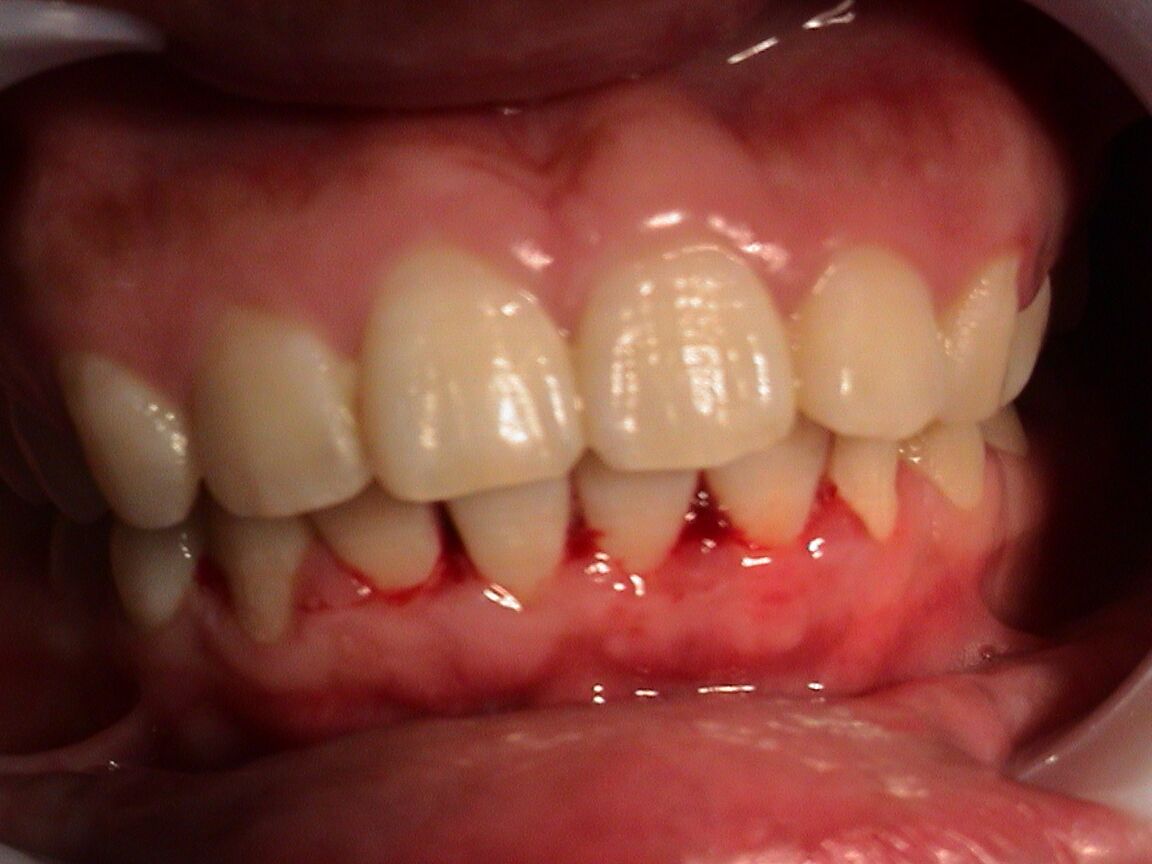

大部分的牙齿出血是因为没有注意口腔卫生习惯以及牙周疾病引起的,虽然不会有明显的痛感,如果一直没有得到缓解的话,可能会导致各种疾病接踵而来,牙齿出血怎么办呢。

导致牙齿出血的原因有很多比如蛀牙、缺乏维生素c以及患上牙龈炎,牙龈炎是导致牙齿出血的最常见原因,因为在牙齿上会含有大量的牙结石和牙垢堆积,从而刺激到牙龈,导致牙龈处于水肿和充血状态,稍微受到刺激时就会流血。